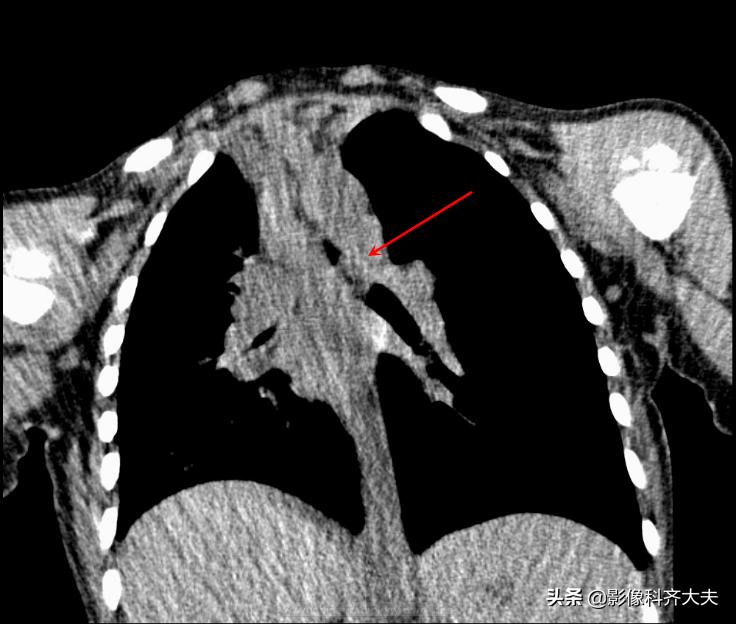

病例2、病史:患儿,男、1岁9个月,咳喘20天。家属否认异物吸入史。

图为正位普通X线片,显示左侧明显肺气肿改变,提示左侧支气管异物可能,因家属否认异物吸入,遂进一步做CT确诊。

CT冠状位重建明确显示左侧自气管阻塞,有明确异物的存在,红色箭头所示。